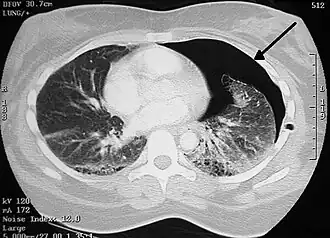

Les maladies ou les évènements préjudiciables qui peuvent affecter la respiration sont nombreux. La médecine définit les maladies respiratoires comme celles qui endommagent ou perturbent le fonctionnement des organes de la ventilation (l'appareil respiratoire au sens anatomique). La pneumologie traite ainsi de tous les troubles qui concernent les poumons, la plèvre, les bronches ou la trachée.

Une atélectasie désigne la rétraction d'alvéoles pulmonaires, voire l'effondrement d'un lobe ou du poumon entier. Dans le premier cas, c'est le blocage d'une bronche qui produit l'affaissement de la partie privée d'air. Dans le second cas, c'est l'entrée d'air dans la cavité pleurale qui provoque un pneumothorax : le poumon se décolle de la cage thoracique.